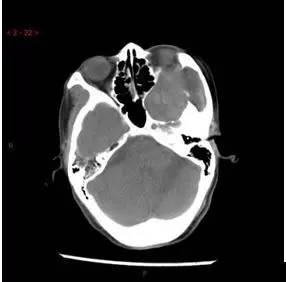

CT平扫轴位

解析:本病例为中颅窝至颞下窝沟通性病变,对周围骨质主要呈膨胀压迫性改变,伴囊变、出血。